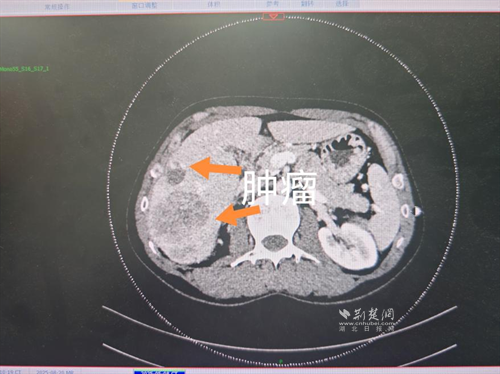

經(jīng)過肝膽外科牽頭組織的多學(xué)科MDT會(huì)診,團(tuán)隊(duì)確認(rèn)其適合接受當(dāng)前國(guó)際先進(jìn)的釔90樹脂微球選擇性內(nèi)放射治療。治療僅一個(gè)月后,患者病灶即從10cm縮小至6cm;術(shù)后六個(gè)月復(fù)查顯示,病灶體積進(jìn)一步縮小近40%,影像學(xué)檢查提示完全緩解,臨床分期成功轉(zhuǎn)化,達(dá)到手術(shù)切除標(biāo)準(zhǔn)。